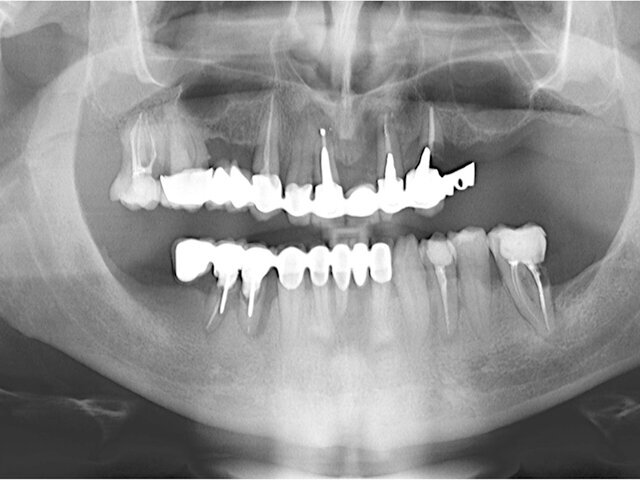

Panoramatický RTG snímek situace před ošetřením

Stanko: „V tomto případě Nino vyjádřil přání zahájit ošetření pouze v horní čelisti. Prvním krokem v našem postupu bylo zhotovit panoramatický RTG snímek a CT sken. Na panoramatickém RTG snímku vidíme mnoho problémů se stávajícími zuby. Nino měl závažnou parodontózu, která postihovala všechny zuby v horní i dolní čelisti. Mnoho zubů zde selhávalo vlivem zubního kazu a dřívějších špatných dentálních náhrad. Jedinou schůdnou možností bylo extrahovat Ninovi všechny zuby v horní čelisti a rehabilitovat celý oblouk. Poté jsme promluvili s Ninem a vysvětlili mu problémy, které měl v horní čelisti a možnosti ošetření. Všichni jsme se shodli na tom, že by pro něj byla nejlepší možností náhrada kotvená šroubky. Poté jsme udělali CT sken Ninovy horní čelisti za účelem vyhodnocení našich chirurgických možností.“